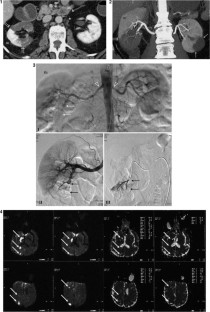

Fig. 1–4